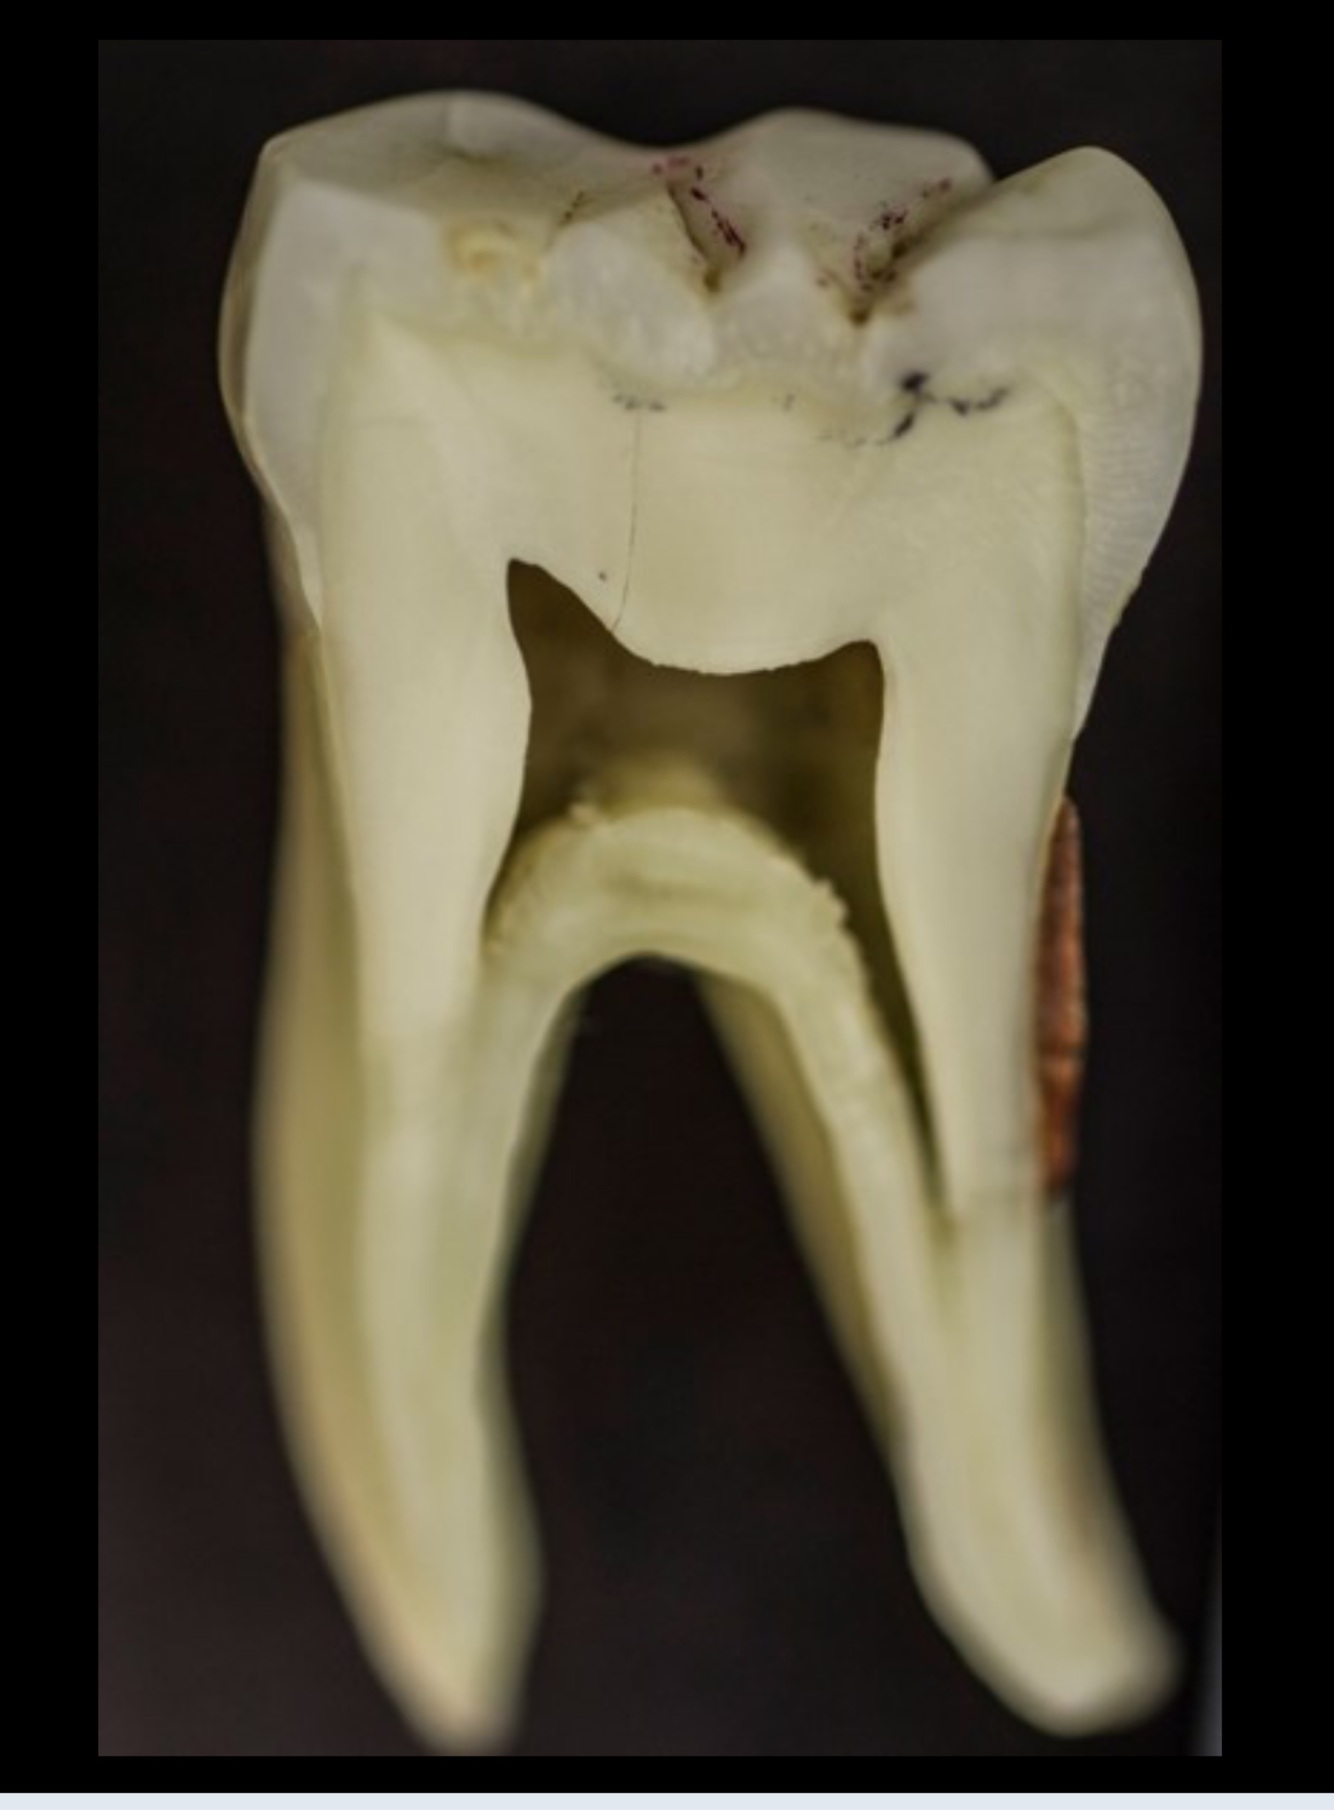

3

Q

The RCT done on:

Upper premolar

Upper molar

Lower premolar

Lower molar

A

Typically, how many root canals are found in a lower first molar?

2

4